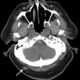

Occipital scalp defect and valvular pulmonary stenosis